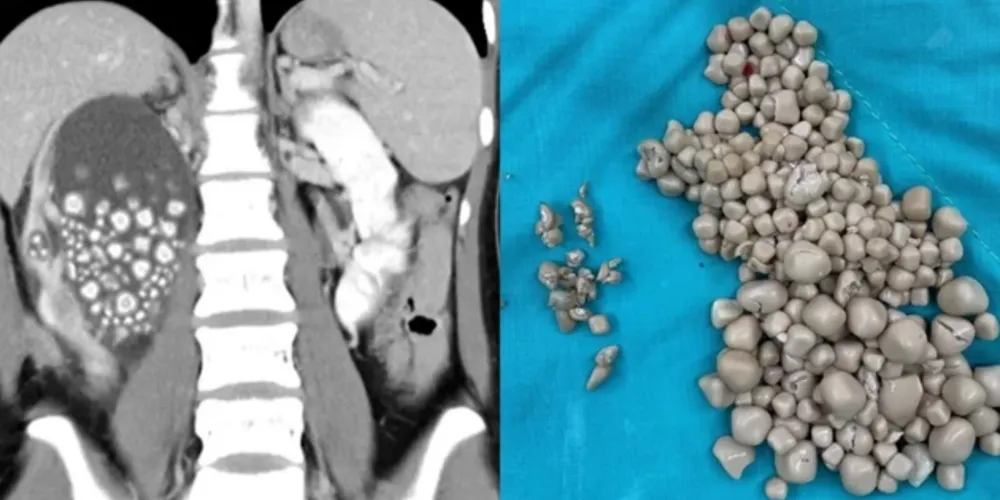

Uma jovem de 20 anos passou por uma cirurgia de emergência em Taiwan para retirar mais de 300 pedras de um dos seus rins. De acordo com o comunicado do Hospital de Chi Mei, onde ela foi atendida, ela compareceu à emergência sentindo febre e dores no quadril.

As maiores pedras tinham cerca de 2 cm de diâmetro. Apenas o rim esquerdo foi atingido.

Contudo, foi necessária uma nefrolitotripsia percutânea, procedimento considerado minimamente invasivo, em que as pedras são retiradas por um pequeno corte feito nas costas. A paciente recebeu alta poucos dias depois do procedimento.